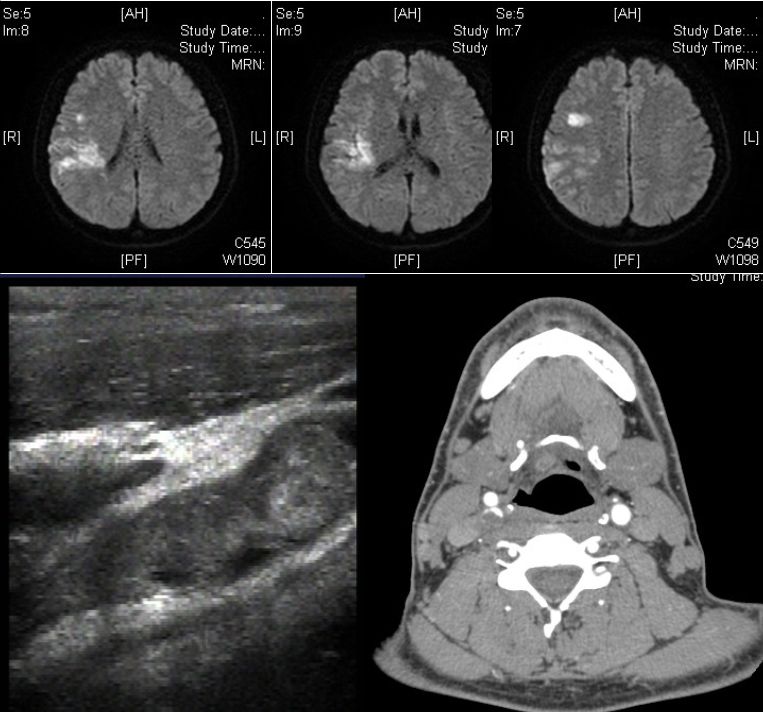

男性35岁。因头晕、左侧肢体无力半天入院。既往:发现血压偏高7-8年;嗜烟酒。查体:血压120/80mmHg,左侧偏瘫。实验室检查:红细胞 5.62*1012/L,Hb185g/L,抗磷脂抗体阴性。

答案:颈内动脉巨大漂浮血栓。颈动脉自由漂浮血栓(附着于血管壁的瘦长血栓,其远端大部仍有栓周血流)罕见,文献报道不超过150例。最常见的病因为动脉粥样硬化或溃疡斑块,也见于高凝状态、高纤维蛋白原血症、缺铁性贫血、血小板增多症、兴奋剂使用者。治疗以抗凝和稳定斑块为主。不常规考虑血管内治疗。因为:1)该血栓为延伸性,而非堵塞性;2)患者神经功能缺损相对轻;3)由于再发栓塞的风险很高,应当避免针对血栓的机械操作。若患者的临床症状恶化,应当进行紧急的机械取栓治疗(如抽吸血栓)。病情稳定后可行颈动脉内膜剥脱术。

患者,21岁女性,患者3小时前做某手术后突 发右侧肢体乏力、意识不清。

发病24小时磁共振:

答案:脑型脂肪栓塞综合征。患者做了自体脂肪填充术。脂肪栓塞综合征(fat embolism syndrom,FES)是指直径为10~40μm的血管内脂肪颗粒阻塞血管腔而引起的一系列病理生理改变的临床综合征。FES常发生于骨创伤及骨手术病人。FES潜伏期为6~24h,FES 的典型三联征为低氧血症、意识障碍和瘀斑。